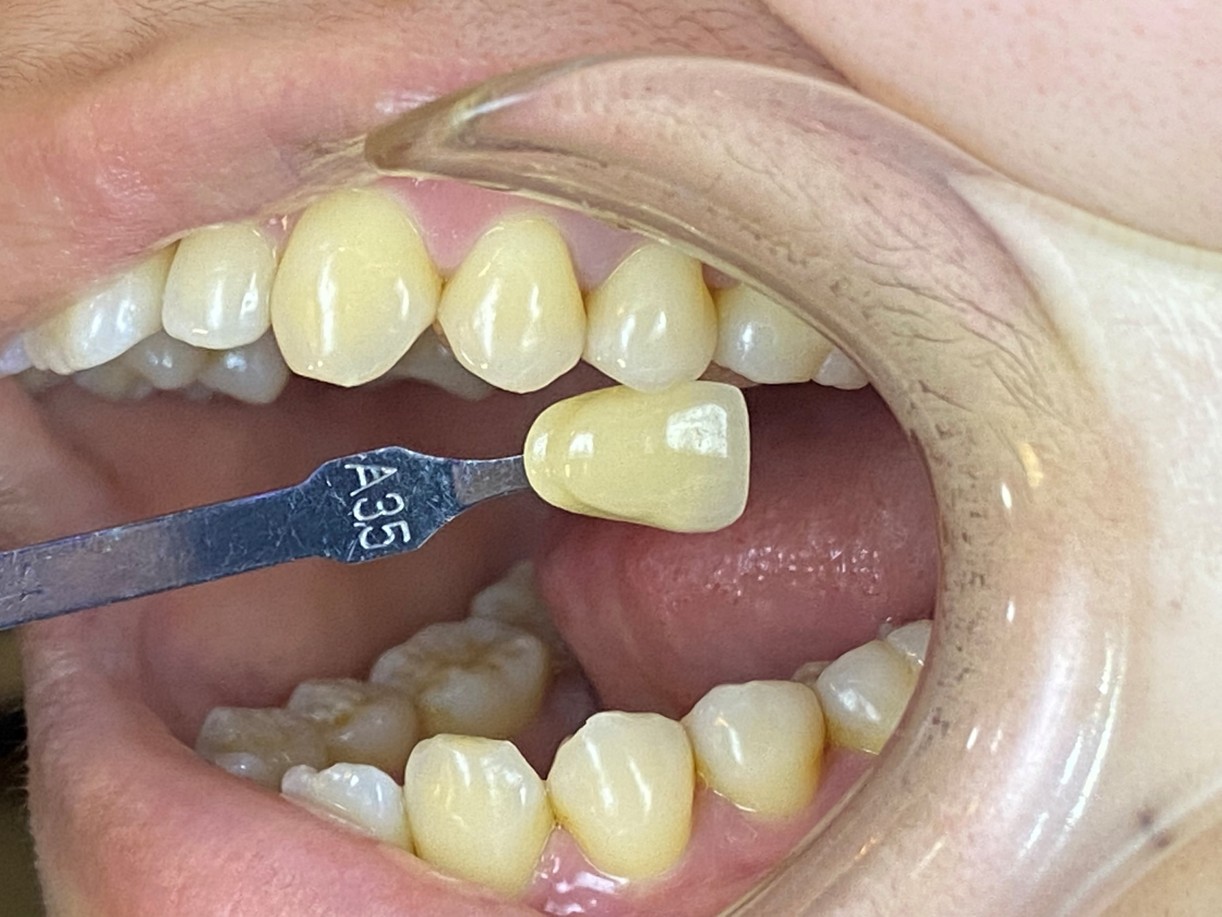

照相比色